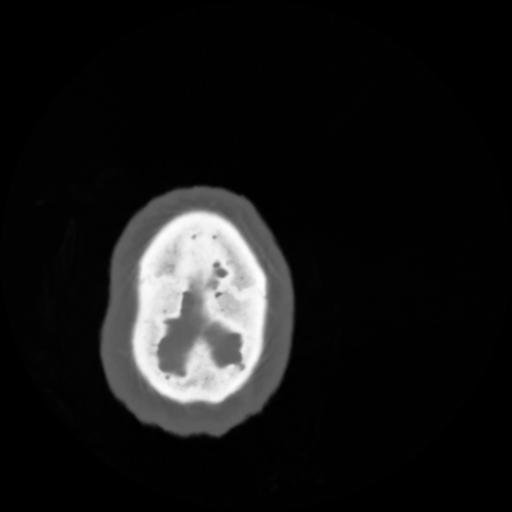

4 CEREBRO,,Vol,0.5,CEREBRO,,